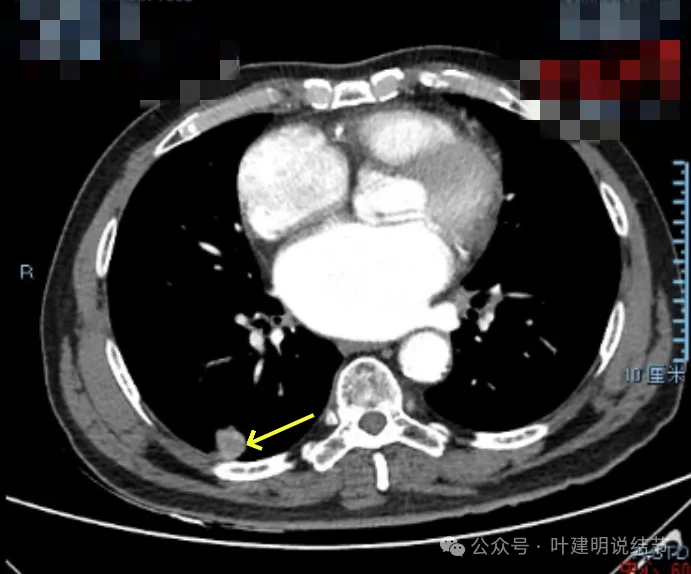

右下新增病灶,混合密度,整体轮廓较清,瘤肺边界欠清。

有小血管进入,边缘毛糙。

局部有毛刺,但不够锐利;病灶感觉有一层晕似的,邻近胸膜下也有淡磨玻璃影。

实性密度为主,周围少许很淡的磨玻璃影。

边缘不平有毛刺,但不锐利;贴着胸膜但无明显牵拉。局部表面有浅分叶似的,但总体膨胀感不够。

病灶表面不光滑,边上有晕,邻近有淡磨,贴着胸膜无牵拉。

病灶边缘欠清晰,瘤肺边界稍模糊。较宽的基底贴着胸膜。

病灶有血管进入,有浅分叶,实性为主,邻近胸膜有片状淡磨玻璃影,近胸膜无牵拉。但有一定膨胀性。

病灶实性,与血管关系较为密切。

血管走向病灶,但似乎没有被病灶影响,有向内侧的分支甚至没有哪怕一点凹向病灶侧。整体显得偏模糊。

边缘区域杂乱,边糊。

增强纵隔窗见病灶内部的密度好像低于周围区域,像坏死。

邻近胸膜无牵拉,灶内有低密度区,局部有点状液性密度。邻近胸膜较为广泛的增厚或胸膜反应。

病灶与胸膜接触面宽,病灶内部密度较低。